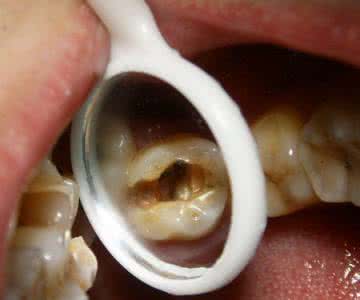

龋齿的食疗

对于龋齿病症的治疗,除了使用消炎解毒药以及手术拔除等医学手段外,还要在饮食上多食用富含钙、氟、维生素D、维生素B1以及多纤维素食物,而忌食糖类及酸性食物。